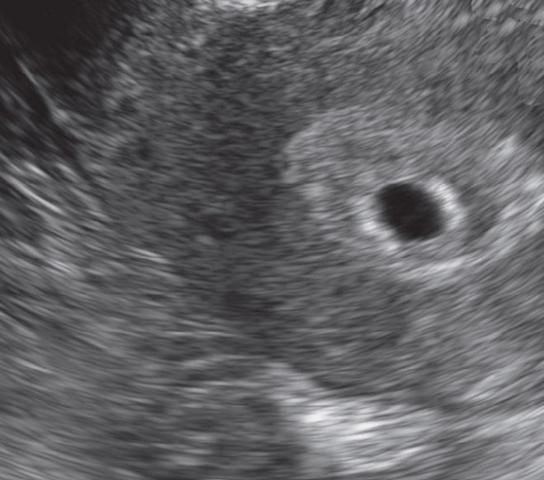

Ultraschall bei der Einnistung:

Der Ultraschall ist ein wichtiger diagnostischer Test, um den Zeitpunkt der Einnistung zu bestimmen. In den ersten Wochen einer Schwangerschaft kann der Arzt mit Hilfe des Ultraschalls feststellen, ob die Eizelle erfolgreich in die Gebärmutterschleimhaut eingebettet ist.

Zu Beginn der Schwangerschaft ist es möglich, dass der Embryo noch nicht sichtbar ist. Der Arzt kann jedoch Anzeichen für eine erfolgreiche Einnistung erkennen, wie zum Beispiel eine verdickte Gebärmutterschleimhaut oder das Vorhandensein eines Schwangerschaftssacks.

Etwa ab der sechsten Schwangerschaftswoche wird der Embryo selbst sichtbar. Der Arzt kann dann die Entwicklung des Embryos beobachten und mögliche Probleme frühzeitig erkennen. Es können auch Informationen über die genaue Dauer der Schwangerschaft und den voraussichtlichen Geburtstermin gewonnen werden.

In einigen Fällen kann es vorkommen, dass sich die befruchtete Eizelle außerhalb der Gebärmutter einnistet, zum Beispiel im Eileiter oder in der Bauchhöhle. Diese sogenannten Eileiterschwangerschaften oder Bauchhöhlenschwangerschaften sind gefährlich und müssen medizinisch behandelt werden. Mit Hilfe des Ultraschalls kann der Arzt diese abnormale Einnistung erkennen und entsprechende Maßnahmen ergreifen.

Der Ultraschall bei der Einnistung bietet also wichtige Informationen über den Verlauf einer Schwangerschaft und ermöglicht es dem Arzt, mögliche Probleme frühzeitig zu erkennen und zu behandeln.